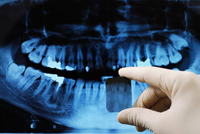

1. check-ups & digital x-rays

Dr Angela recommends that everyone has a check-up every six months. This |